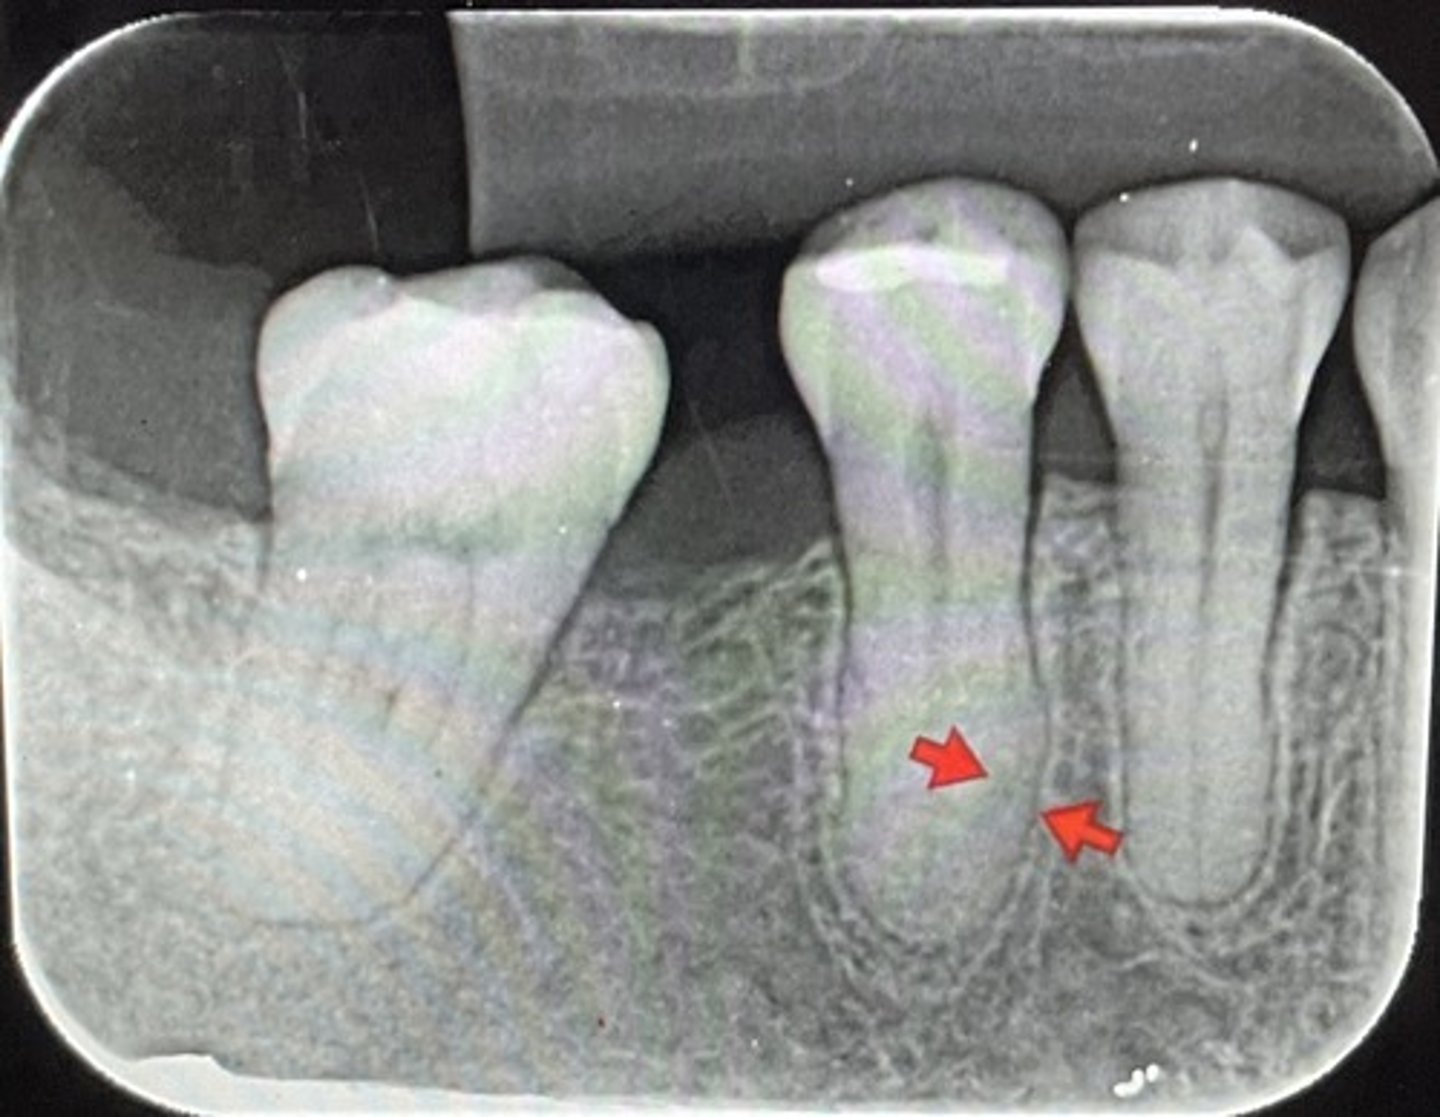

Hypercementosis

What are the red arrows representing?